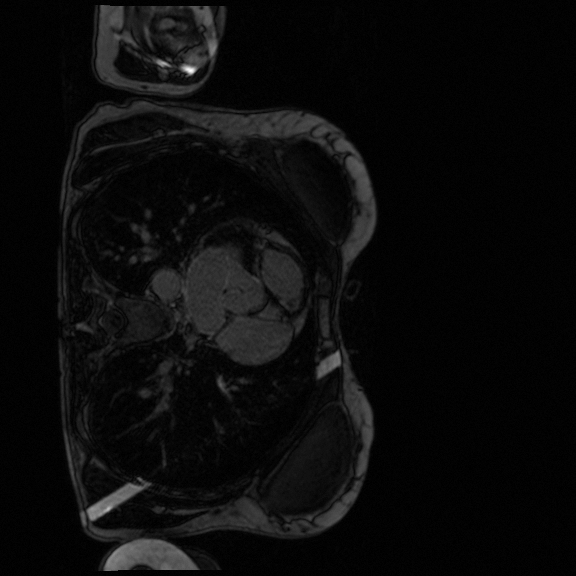

Late gadolinium enhancement magnetic resonance imaging (LGE-MRI) is typically used to provide quantitative information on atrial scars [25]. In this measurement, location and size in the left atrium (LA) indicate pathology (i.e., LA scars) and progression of atrial fibrillation [12].

Nowadays, deep learning models have been widely used to segment LA cavities and quantify LA scars from LGE-MRIs [3] to help radiologists with initial screening for quick pathology detection. Meanwhile, LGE-MRIs are often collected by multiple scanners and possibly in low imaging quality. Each of them produces inconsistent domain information [14], including different contrast and spatial resolutions. (1) Promoting the generalization of a segmentation model against domain inconsistency becomes another challenge.

In terms of LA scar prediction, prior work predicts LA and LA scars separately without considering the relationship between them [16]. Meanwhile, the size of the scars is relatively insignificant, bringing difficulties in the prediction. Fortunately, LAs are much easier to be predicted, while LA scars are often detected near identified LA boundaries Fig. 2. Inspired by [29], we believe that combining the prediction of LAs and LA scars can be expected to improve scar segmentation performance.